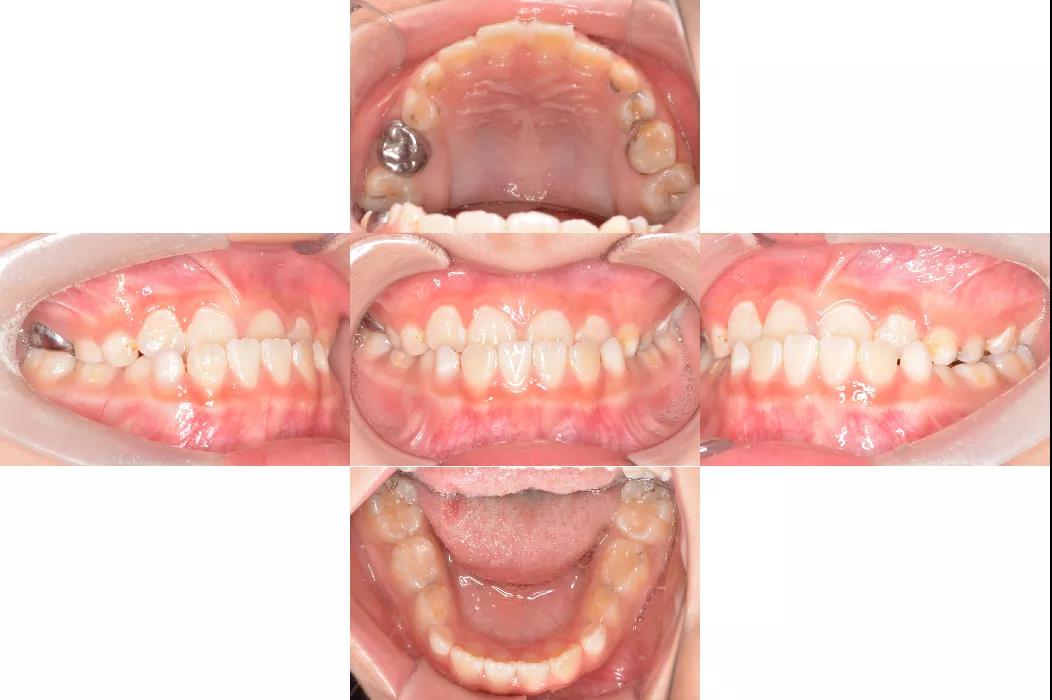

图片